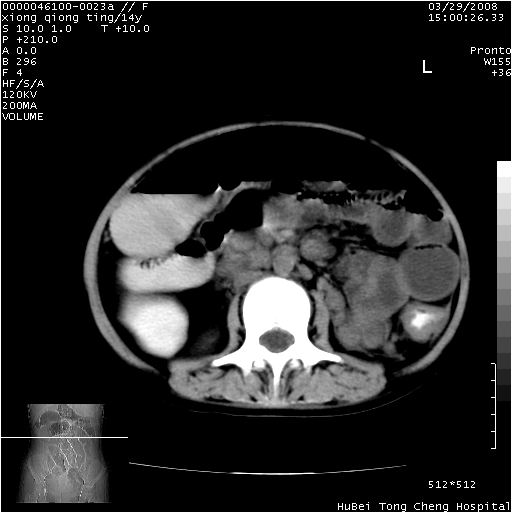

中下腹及盆腔ct轴位平扫+增强扫描(层厚10mm,螺距1.0,重建间隔10mm),图像如下:

(注:患儿检查当日上午9时口服胃肠道对比剂,下午3时许行ct扫描检查,未行对比剂直肠保留灌肠,检查当日患儿腹泻)

中下腹及盆腔ct轴位扫描(ps+ce)提示:腹部肠管明显充气扩张,并见数个不同宽度之气液平面;疑不全性肠梗阻或肠郁张。临床会诊考虑为患儿腹泻,肠郁张所致;后来未经特殊处理,患儿大便恢复正常,亦无腹胀。